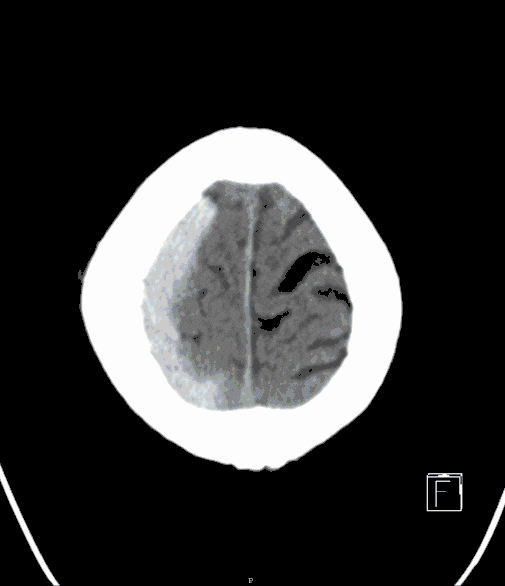

Traumatic Brain Injury

Depending on the severity of the injury, potentially life-threatening situations may arise from increased pressure within the cranial cavity, requiring surgery as a last resort in certain circumstances. In other cases, immediate surgery may be required first (impression fractures, epidural and subdural hemorrhages).